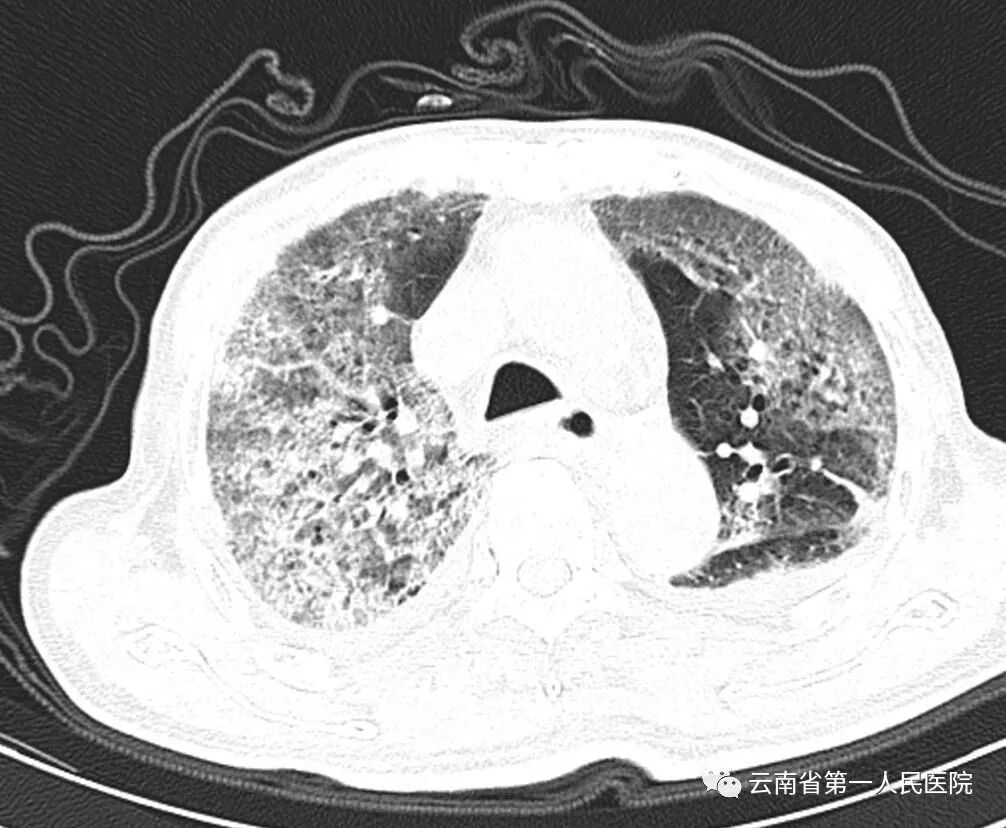

白肺不是一种疾病,而是较严重肺炎的影像学表现。我们的肺是由肺泡组成的,正常情况下肺泡里充满了空气,进行CT或X线检查时,射线穿过肺泡,影像表现为黑色。 但当肺部感染或炎症时,毛细血管渗漏加重,大量渗出液和炎性细胞渗漏到肺泡和肺间质,肺中的气体含量减少,这样X射线就穿不透,在影像学上的表现就是肺变白了,并不是说肺组织本身变成了白色。

很多疾病都可能引起白肺,如严重的病毒性肺炎、细菌性肺炎、真菌性肺炎、非感染性炎症渗出都可能导致白肺。 并不是只要肺部出现了炎症都叫白肺,一般肺部炎症比较重、渗出液较多,白色影像的面积达到70%—80%时,才称为白肺。